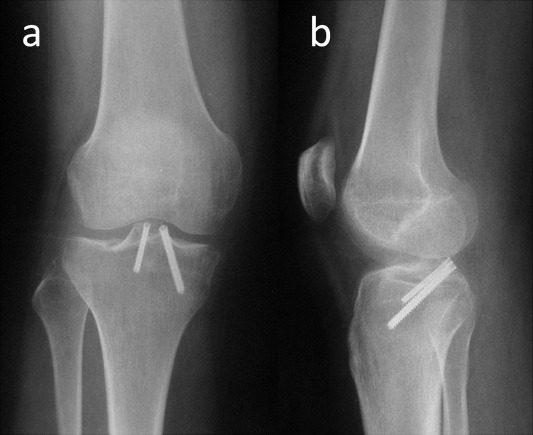

A 20-year-old female was admitted to the emergency department after sustaining a motorcycle accident. On presentation she was unable to weight bear and there was slight knee effusion without ecchymosis or deformity. On physical examination, she was keeping her knee in slight flexion and knee range of motion was painful and grossly restricted. Knee medial joint space was tender and varus stress test at 30° of knee flexion demonstrated grade I medial laxity (medial joint space opening less than 5 mm). Further detailed physical examination could not be performed due to intentional guarding, pain and muscle spasm. Plain radiographic examination of the knee demonstrated a marginal fracture of the anteromedial tibial plateau and lateral intercondylar eminence (Fig. 1 ). MR imaging of the knee revealed PCL avulsion fracture, ACL grade II strain and MCL grade I strain. Both menisci were intact (Fig. 2 ).

Fig. 1

Fig. 1.

Anteroposterior (a) and lateral (b) knee radiographs of the patient at initial admission. White circle shows the reverse Segond fracture . White arrow shows the fracture line that extends to the lateral tibial plateau and black arrow shows the PCL avulsion fracture.